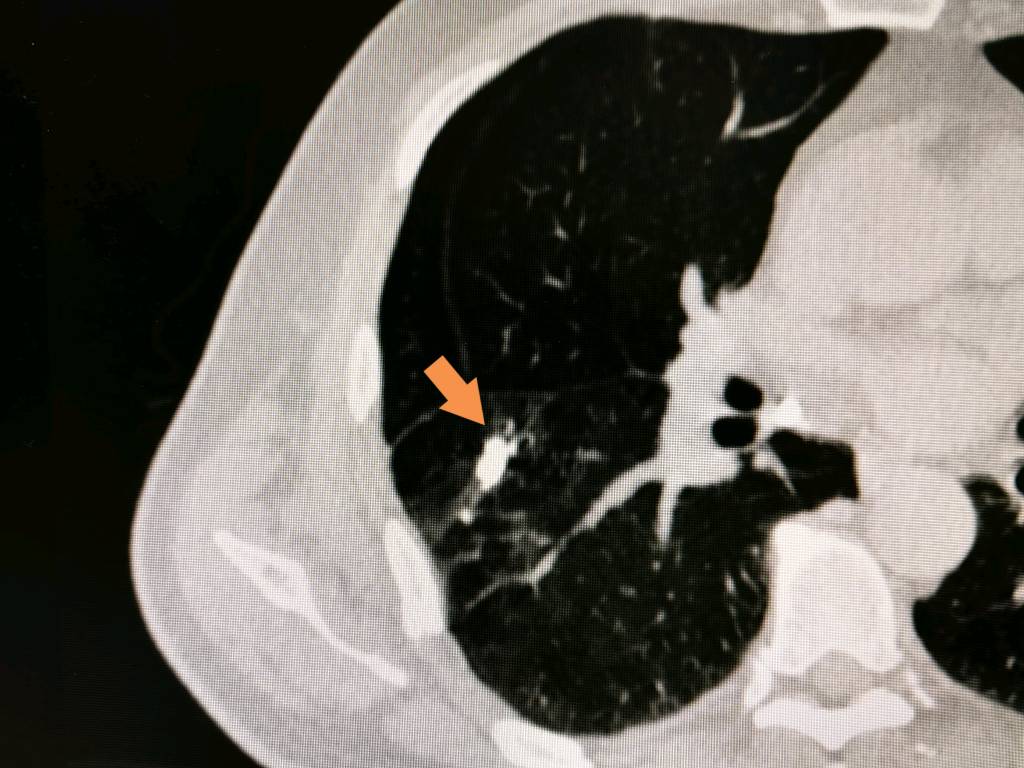

第五种情况:粘液栓

这个发现特别有意思——就像您在扫描的瞬间,肺部或支气管里正好有一口痰被清晰地捕捉到了。它属于暂时的生理性表现,随着呼吸和咳嗽就会被自然排出,与肿瘤完全没有关联。